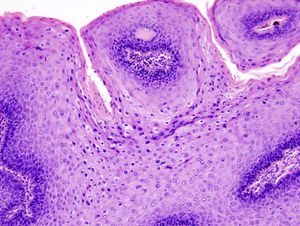

생식기 사마귀는 대부분 육안으로 진단하지만, 필요한 경우 생검을 통해 확진하기도 한다.[52] 작은 사마귀는 전염성 연속종과 혼동될 수 있으므로 주의해야 한다.[53] 조직병리학적으로 생식기 사마귀는 진피 유두가 확대되어 피부 표면 위로 솟아오르는 특징을 보이며, 부전각화증과 HPV 감염의 특징적인 핵 변화(핵주위 부분이 사라지고 핵이 확대됨)를 나타낸다.

생식기 사마귀의 현미경 사진. 특징적인 변화(과각화증, 공포세포, 유두종증)를 보여준다. H&E 염색.

고위험 HPV 감염 여부는 DNA 검사로 확인할 수 있다. 그러나 생식기 사마귀는 저위험 HPV 유형에 의해 발생하므로, DNA 검사가 생식기 사마귀 자체를 진단하는 데 사용되지는 않는다.[44]